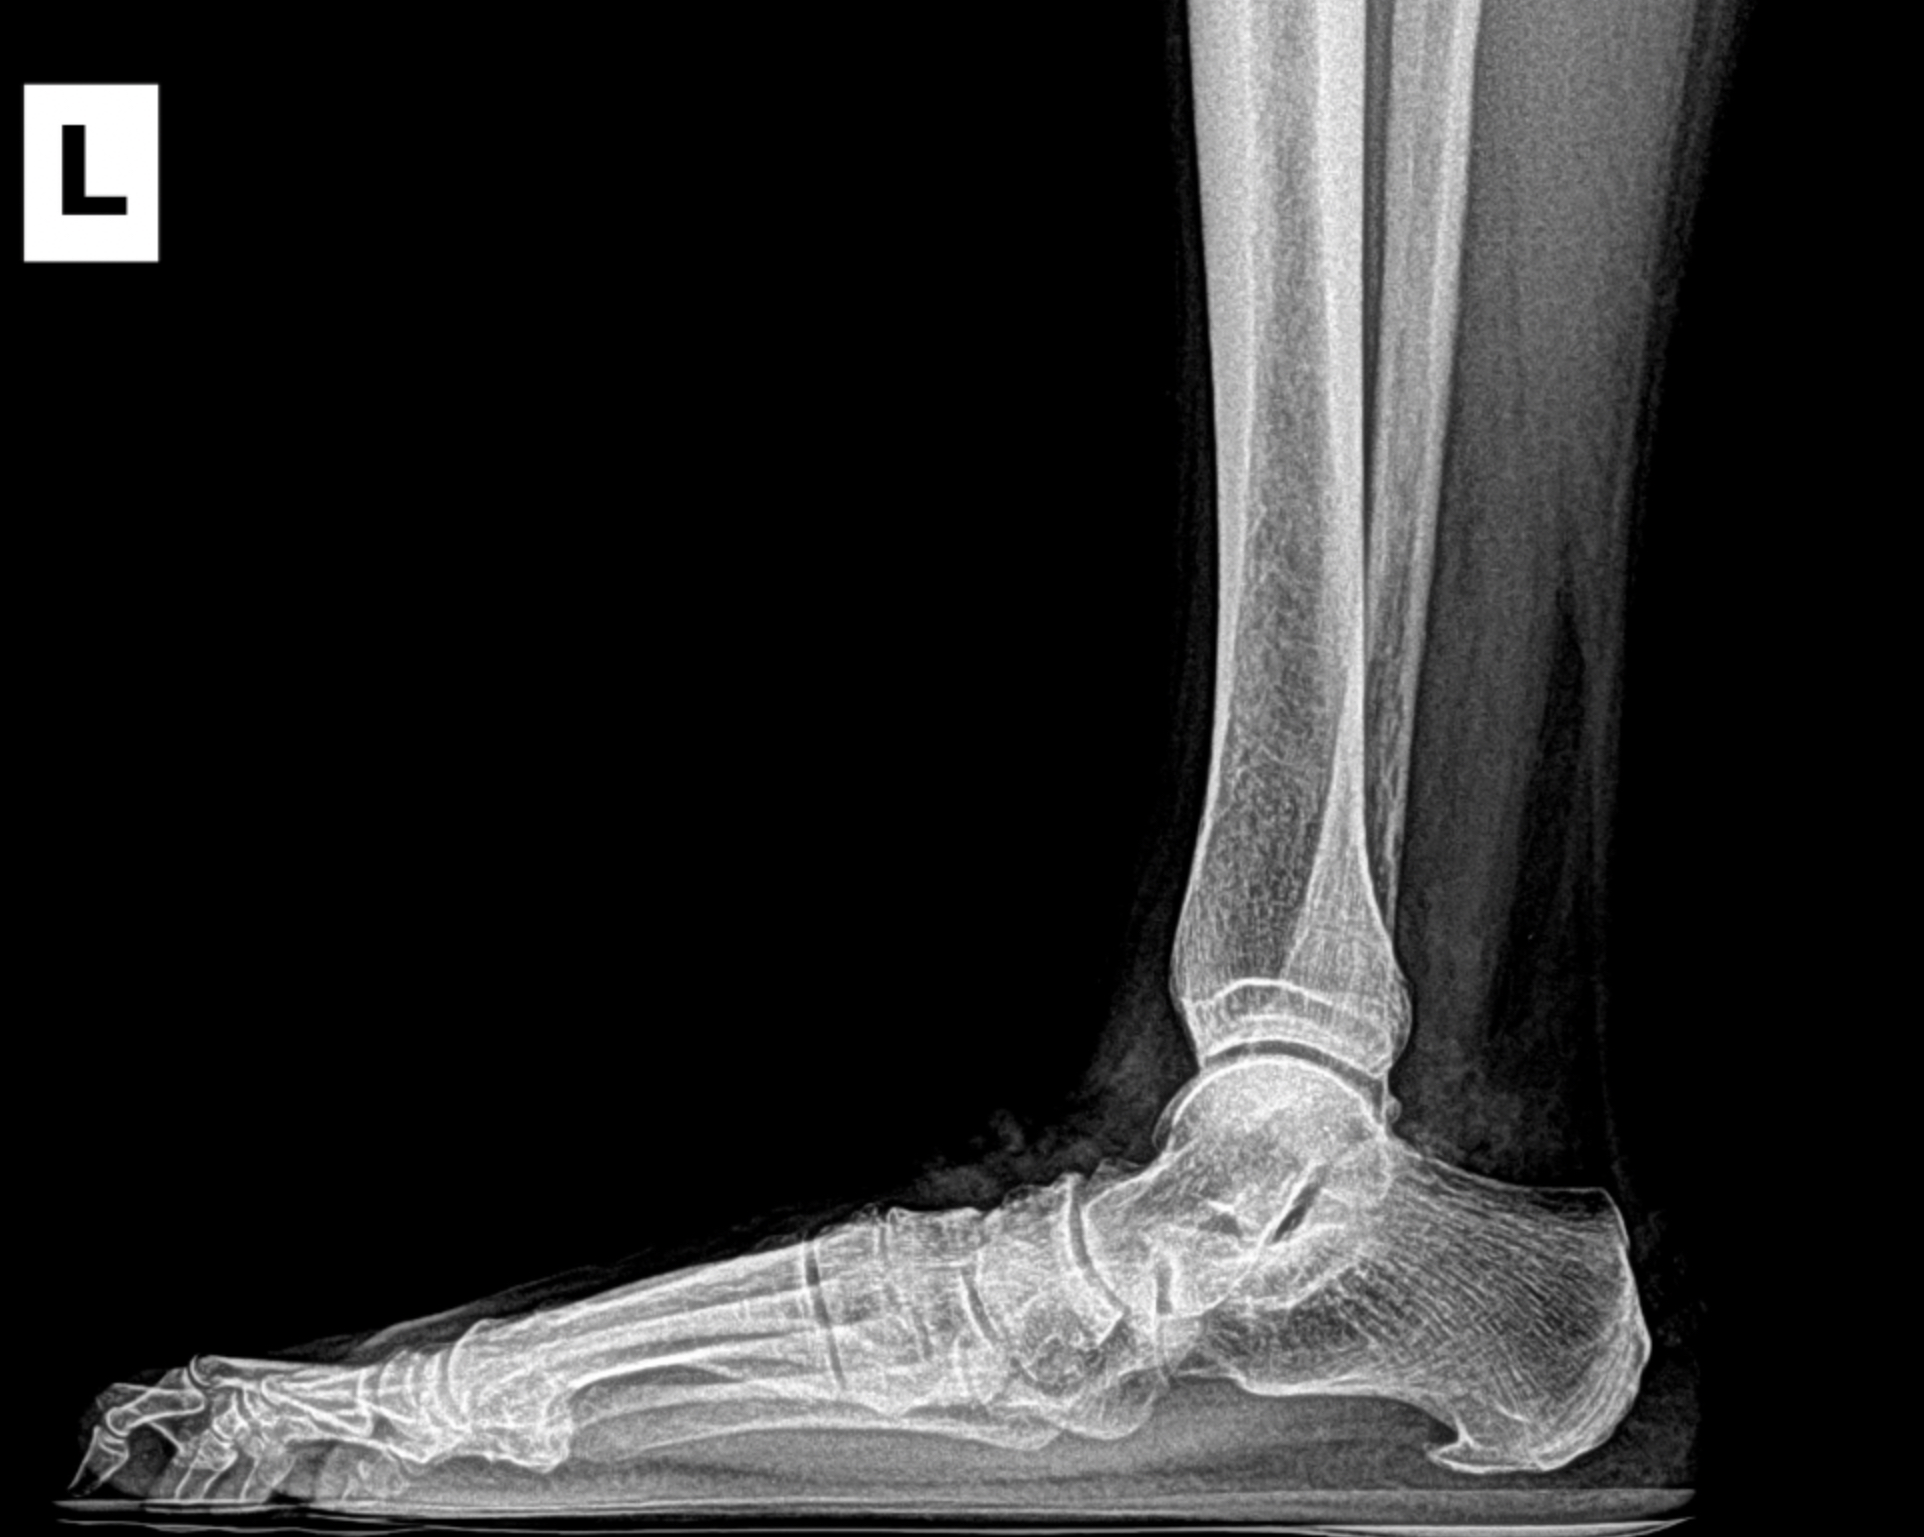

Arthritic flatfoot

Flatfoot deformity

Patient 1

Patient 2